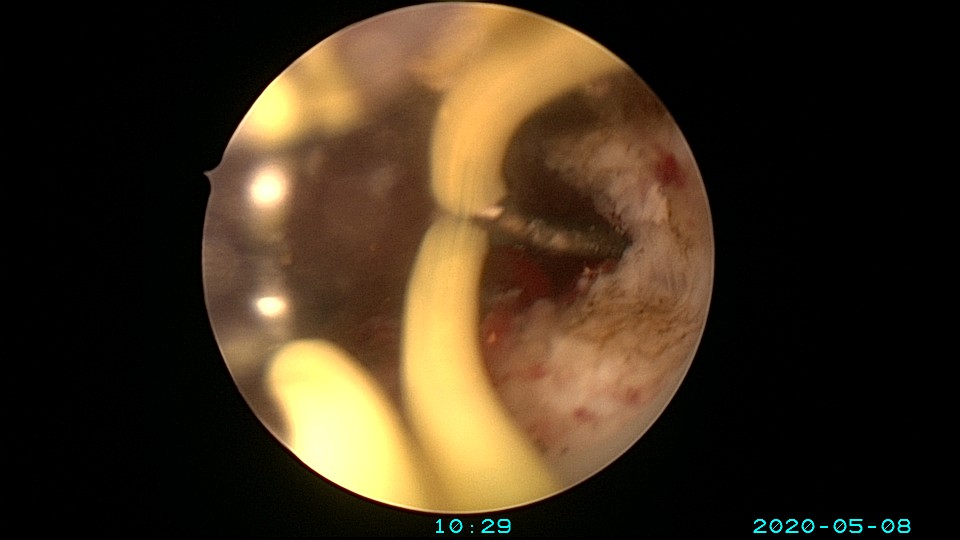

患者32岁,G10P1,剖宫产1次。2020年2月人流术后闭经2+月,2020年5月宫腔镜探查见剖宫产切口憩室,宫颈内口以上广泛封闭粘连,AFS评10分,双极电针分粘效果差,扩张宫颈管,改用双极电切分粘,恢复宫腔形态,显露双侧输卵管开口。2020年6月宫腔镜二探取球囊,宫腔形态正常,双侧输卵管开口可见。2020年10月自然妊娠,2021年2月初的某一天,在电梯里,病人的老公认出我是给他老婆做手术的医生,表达感谢之余,讲病人因先兆流产在产科保胎,情绪不稳定,甚至想终止妊娠,医生及家属努力安抚病人。2021年5月,36+3周剖宫产分娩。现37岁,G11P2。